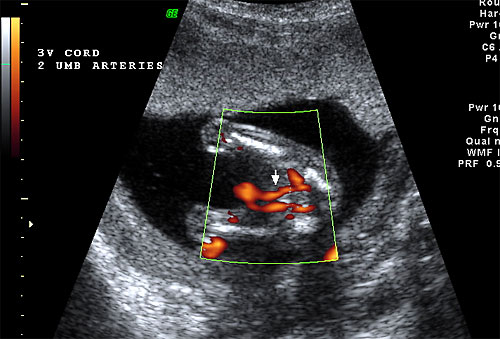

Normal 16 week 3 vessel cord by color flow Doppler |